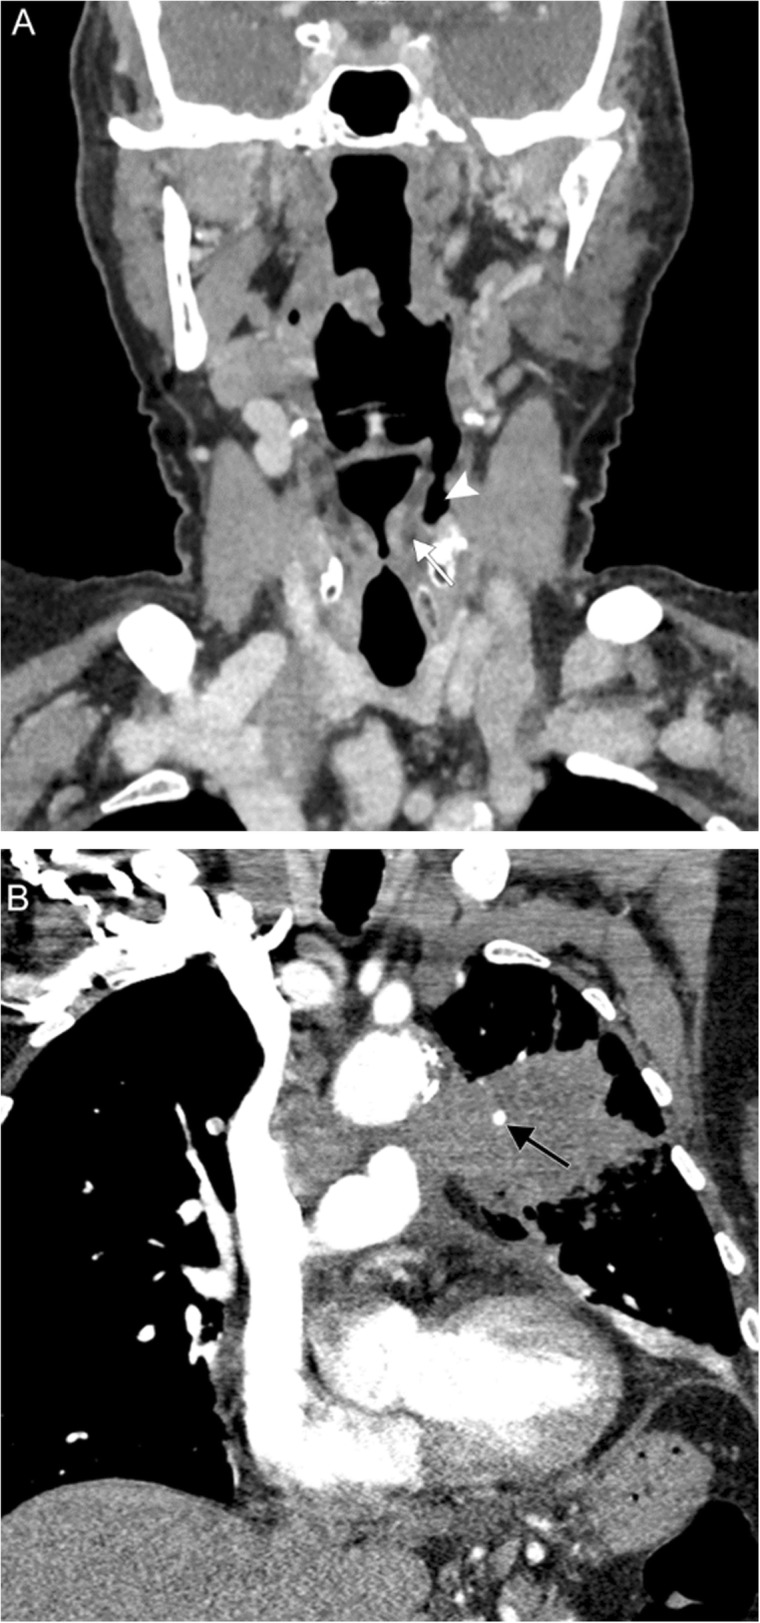

Fig. 21.

Endocarditis. A 41-year-old previously healthy man presents with intermittent hoarse voice and unexpected weight loss. Axial contrast-enhanced CT images through the larynx (a) and mediastinum (b) reveal left vocal fold rotation (white arrow) and lymphadenopathy surrounding the left carotid and subclavian arteries (white arrowheads). A coronal CTA image (c) reveals an ascending aortic aneurysm (black arrows). Echocardiogram (d) reveals a bicuspid valve with vegetations (gray arrow) and severe aortic stenosis. Overall, findings are consistent with compression/stretching of the left recurrent laryngeal nerve due to reactive lymphadenopathy and a dilated aortic arch in the setting of endocarditis

Fig. 22.

Pulmonary artery aneurysm. A 78-year-old man with advanced congestive heart failure secondary to congenital pulmonary artery stenosis status post multiple corrective surgeries, now presenting with progressive shortness of breath and speaking difficulty despite adequate management of heart failure. Axial CTA image (a) through the mediastinum reveals aneurysmal dilatation of the left pulmonary artery (white arrows). An axial CTA image through the larynx (b) reveals thickening of the left aryepiglottic fold (white arrowhead) and dilatation of the left piriform sinus (black arrow). A coronal CTA image (c) demonstrates effacement of the aortopulmonary window (black arrows) by the pulmonary artery aneurysm (white arrows) with presumed compression of the left recurrent laryngeal nerve